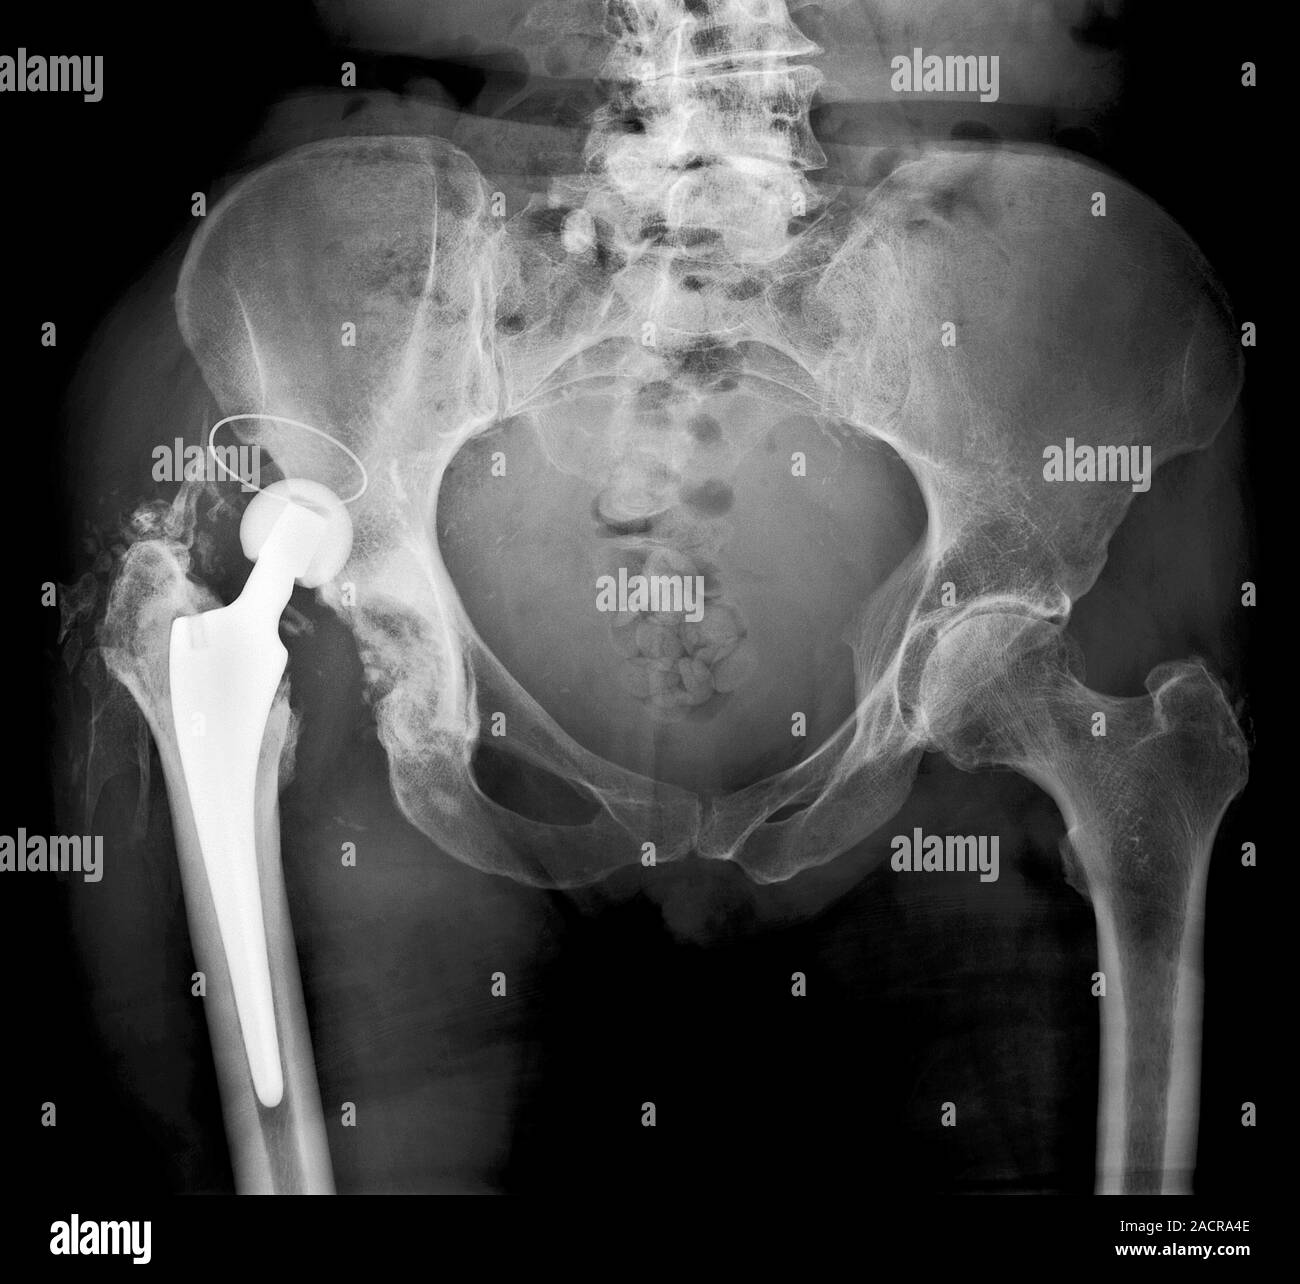

A magnified view of the dislocated right Exeter total hip replacement,... Download Scientific

Dislocated hip replacement. Xray of the pelvis of a patient who's total hip replacement of the Hip Replacement Dislocation Xray  Hip dislocations are traumatic hip injuries that result in femoral head dislocation from the acetabular socket. This overview focusses on the normal findings and complications of. Radiography is the primary imaging method for the evaluation of total hip arthroplasty. Diagnosis can be made with hip radiographs to determine the direction of. Hip dislocation (dislocation of the femoral head from the. Hip Replacement Dislocation Xray.